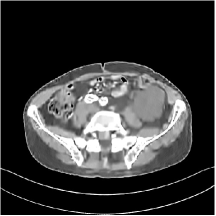

III.C.2. Simulation Framework, Reconstruction Results, and Comparisons

The synthesized low-dose clinical measurements are simulated from regular-dose images at a resolution of mm with a fan-beam CT geometry corresponding to a monoenergetic source at incident photon intensity . The sinograms are of size . The width of each detector column is mm, the source to detector distance is mm, and the source to rotation center distance is mm. We reconstruct images of size with the pixel size being mm mm.

We conducted experiments on one test slice used for parameter tuning (L067-slice 120) and four independent test slices (L109-slice 90, L192-slice90, L333-slice140, L506-slice 100) of the Mayo Clinic data. For PWLS-EP, we ran iterations using relaxed OS-LALM and set regularization parameter . We used the same as the phantom experiments for Algorithm 2. The process of selecting a general set of reconstruction parameters () for the Mayo Clinic test slices is identical to that for the XCAT phantom in Section III.B.2. The selected regularization parameter and the parameters that control the sparsity of the coefficient maps are for ST, , , , , for MARS2, , , , , , , for MARS3, , , , , , , , , , , for MARS5, and , , , , , , , , , , , , , , for MARS7, respectively.

Figs. 8, 9, 10, and 11 show the reconstructions of the four independent slices using the FBP, PWLS-EP, PWLS-ST, PWLS-MARS2, PWLS-MARS3, PWLS-MARS5, and PWLS-MARS7 schemes, respectively. Additional Mayo Clinic experimental results of the parameter tuning case (Fig. 15) are shown in the supplementary document. Table 1 lists the RMSE and SSIM values of reconstructions of the four independent test slices, with the best values bolded. Generally, the five and seven layer models provided the best RMSE and SSIM values. They outperform the single-layer model by HU in RMSE on average. However, the MARS5 and MARS7 models perform similarly. In order to strengthen the benefits of the multi-layer model, Table 2 lists the RMSE of the reconstructions in four different ROIs (shown in the reference of Fig. 11) with seven methods for slice 100 of patient L506. By observing the reconstructed images, we see that although the ST model achieves a cleaner reconstruction result than FBP and PWLS-EP, it still sacrifices some sharpness of the central region and suffers from loss of details. The deeper models have a somewhat more positive effect in terms of maintaining subtle features, which is clearly more essential to clinical diagnosis. Furthermore, as we will discuss later, after considerable parameter tuning, we found that the information contained in residual maps is gradually decreased with the number of layers, eventually vanishing at some layer, which suggests that very deep unsupervised models might not offer significantly better image quality.